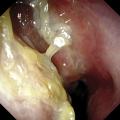

L’examen nasofibroscopique note le plus souvent un œdème muqueux diffus, des sécrétions mucopurulentes très épaisses (du fait de la déshydratation du mucus) ou parfois des polypes inflammatoires bilatéraux(fig. 1) . Le contexte clinique permet toutefois d’éliminer le diagnostic de polypose nasosinusienne qui répond à des mécanismes physiopathologiques différents dominés par l’infiltration inflammatoire riche en polynucléaires éosinophiles. La polypose nasosinusienne est par ailleurs fréquemment associée à un asthme (40 % des cas) ou à une intolérance aux anti-inflammatoires non stéroïdiens (15 % des cas), ce qui n’est pas observé dans la rhinosinusite associée à la mucoviscidose.

L’examen nasofibroscopique note le plus souvent un œdème muqueux diffus, des sécrétions mucopurulentes très épaisses (du fait de la déshydratation du mucus) ou parfois des polypes inflammatoires bilatéraux